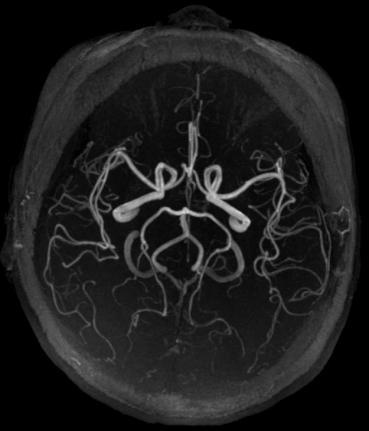

注:图 1 图 2 均为头颅动脉血管磁共振检查结果图片,图 1 为脑梗患者的动脉血管显像,红色箭头处表示该处有血栓堵塞,造成远端血管没有血流通过,以至于远端血管没有显影;图 2 为正常颅脑动脉血管,双侧血管对称显示清楚。